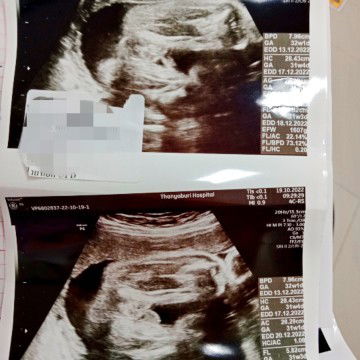

ขอความคิดเห็นแม่ๆหน่อยค่ะ ว่าแบบนี้ผู้หญิงหรือผู้ชาย ตอนช่วงอายุครรภ์4-6เดือนคุณหมอซาวด์ให้บอกผู้หญิงทุกรอบ พอมาเมื่อวันที่19ตุลาที่ผ่านมา ครบ32+2สัปดาห์ คุณหมอบอกน้องน่าจะเป็นผู้ชาย อิแม่แอบกังวล เพราะเตรียมของใช้ลูกเกือบหมดแล้ว แต่แม่แน่ใจว่าได้ลูกสาว #ขอบคุณล่วงหน้านะคะ #ขอบคุณสำหรับคำตอบค่ะ